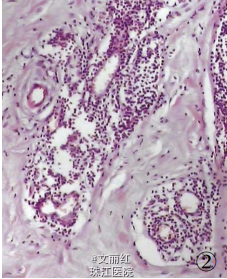

请糖尿病科会诊后,将血糖控制稳定后行肿物切除术。术中见肿物大小12*8*6cm,无包膜,切面实性,大部分为灰白色,质地硬。予以完整切除。冰冻提示良性病变。术后镜检:乳腺间质中含致密的胶原纤维似瘢痕样,小叶及导管周围件较多炎细胞浸润。病理诊断:糖尿病性乳腺病。